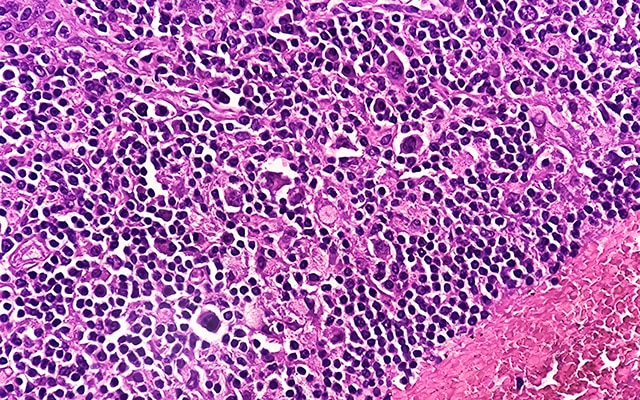

Expanded Approval of Immunotherapy for Hodgkin Lymphoma

- In March 2026, the immune checkpoint inhibitor nivolumab (Opdivo) was approved in combination with the chemotherapy regimen doxorubicin, vinblastine, and dacarbazine for adult and pediatric patients 12 years and older with previously untreated, advanced (stage 3 or 4) classical Hodgkin lymphoma, which is the most common type of Hodgkin lymphoma.

In 2016, nivolumab was the first immune checkpoint inhibitor to be approved for Hodgkin lymphoma, which also marked the first immunotherapy to be approved for any hematologic malignancies. While the original approval of nivolumab was for patients whose disease had relapsed after multiple prior treatments, including autologous hematopoietic stem cell transplantation, its use in combination with chemotherapy has now been expanded as the new standard of care for patients with newly diagnosed stage 3-4 Hodgkin lymphoma.